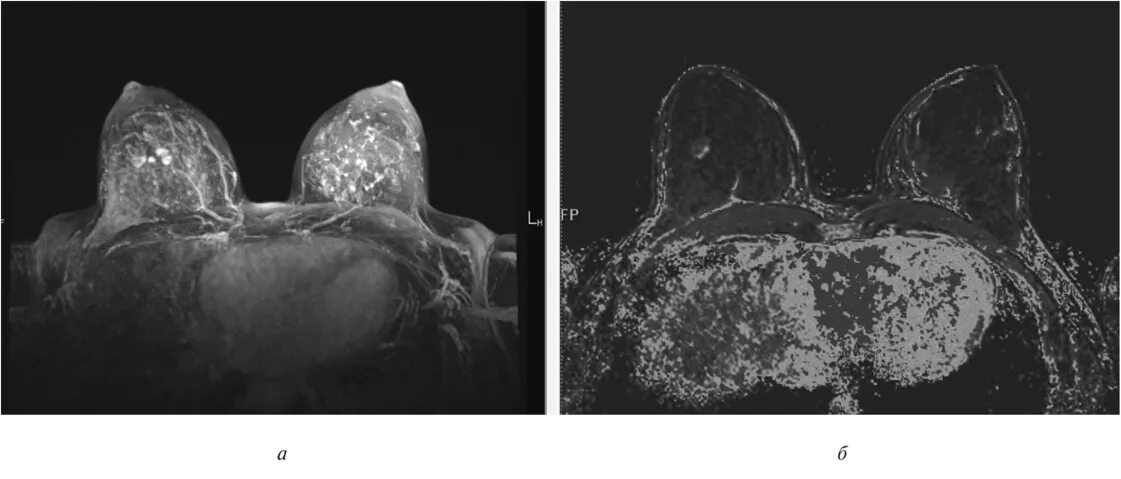

Мрт молочных желез